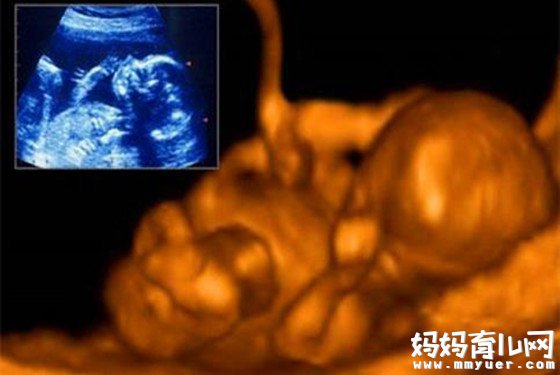

怀孕28周男宝肚型图片

28周的时候孕妈妈宫高在21~24厘米左右,一些孕妈妈这时都会发现自己长了妊娠纹。偶尔觉得肚子一阵阵发硬发紧,这是假宫缩,不必紧张。